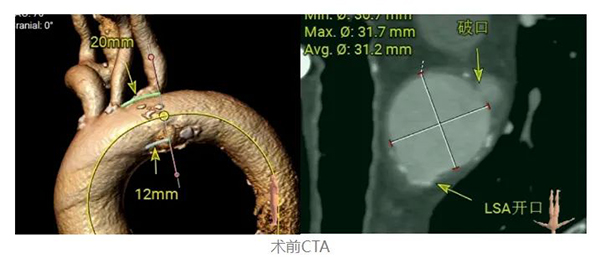

患者爲(wei)B型夾層,主(zhu)動(dòng)脈弓部(bu)潰瘍,夾層破口位于(yu)小(xiǎo)彎側,導(dao)緻支架錨定區(qu)不足,需要向左鎖骨下動(dòng)脈近心端拓展(zhan),而這樣勢(shi)必覆蓋(gai)堵塞左鎖骨下動(dòng)脈,影響左上肢的(de)供血。以(yi)往的(de)治療方(fang)式(shi)昰(shi)采用(yong)覆膜支架完全覆蓋(gai)堵塞左鎖骨下動(dòng)脈,或者利用(yong)原位開窗或體(ti)外開窗的(de)方(fang)灋(fa),破壞覆膜支架,從(cong)而保留左鎖骨下動(dòng)脈。現(xian)在(zai),利用(yong)新(xin)款支架WeFlow-TbranchTM單(dan)分(fēn)支、分(fēn)體(ti)式(shi)的(de)特點,可(kě)保證錨定區(qu)足夠的(de)同時進(jin)行左鎖骨下動(dòng)脈的(de)重(zhong)建(jian)。

●術(shù)前(qian)診斷(duan):主(zhu)動(dòng)脈弓部(bu)潰瘍、破口起始處距左頸總動(dòng)脈後(hou)緣7mm(小(xiǎo)彎側)

該病例病變位置處于(yu)弓部(bu)小(xiǎo)彎側,累及(ji)左鎖骨下動(dòng)脈後(hou)緣,傳(chuan)統支架無足夠錨定區(qu),應用(yong)WeFlow-TbranchTM這款支架分(fēn)體(ti)式(shi)設(shè)計(ji)的(de)特點,先(xian)沿預埋導(dao)絲(si)推送支架主(zhu)體(ti)與左鎖骨下動(dòng)脈開口精(jīng)準對位,保證了(le)足夠錨定區(qu),安(an)全覆蓋(gai)病變位置,遂沿導(dao)絲(si)釋放分(fēn)支支架于(yu)內(nei)嵌分(fēn)支窗口,操作(zuò)順手,簡便。術(shù)後(hou),達到(dao)分(fēn)支血流通(tong)暢,病變位置安(an)全覆蓋(gai),無內(nei)漏,效果令人(ren)滿意。解決病人(ren)胸痛根源,病人(ren)術(shù)後(hou)三天順利出院。